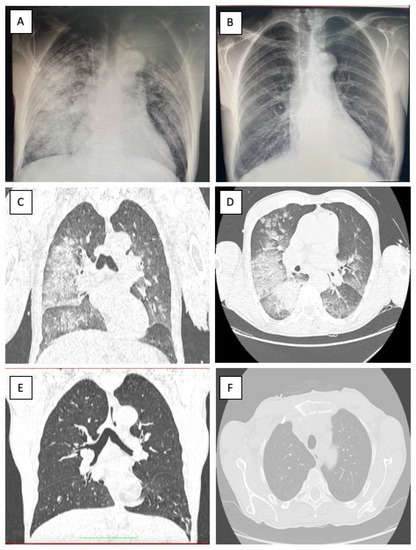

2. Case Report